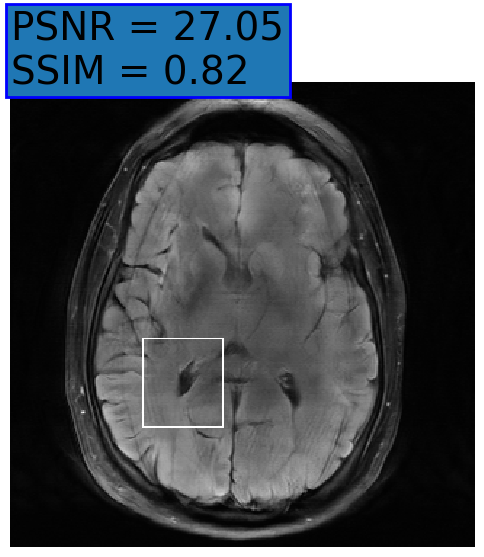

Figure 3: Reconstructions results. Rows 1 and 3: Examples of comparing the ground truth (GT) fully sampled image to the reconstructed images obtained by the three models (1-3), NPB-REC, baseline, E2E-VarNet trained with Dropout, and the NPB-REC std. map at accelerations R=4𝑅4R=4, R=8𝑅8R=8, respectively. Rows 2 and 4: The corresponding annotated ROIS of Nonspecific white matter lesions.

Fig. 3 presents examples of reconstruction results obtained by (1) our NPB-REC approach, (2) the baseline, and (3) Monte Carlo Dropout, for equispaced masks with two different acceleration rates R=4𝑅4R=4 and R=8𝑅8R=8. The reconstructed images predicted by the three models are smoother than the reference image. This is due to the fact that all the models were trained with SSIM loss, which tends to produce overly smooth reconstructions while preserving the diagnostic content and the anatomical features Sriram et al. (2020a). These images can be enhanced by dithering the image by adding a small amount of random Gaussian noise to produce a more textured reconstruction, as proposed in Sriram et al. (2020b).

Table 1 presents the mean PSNR and SSIM metrics, calculated over the whole inference set, for the three models. Our NPB-REC approach achieved significant improvements over the other methods in terms of PSNR and SSIM (Wilcoxon signed-rank test, pmuch-less-than\ll1e-4, except for SSIM values in line W, R=4𝑅4R=4 where they are roughly the same for NPB-REC and Baseline). The improvement in the reconstruction performance can be noted both quantitatively from the metrics, especially for masks with acceleration rate R=8𝑅8R=8, and qualitatively via the images of annotations, where our results show less smoothness than those obtained by Dropout.